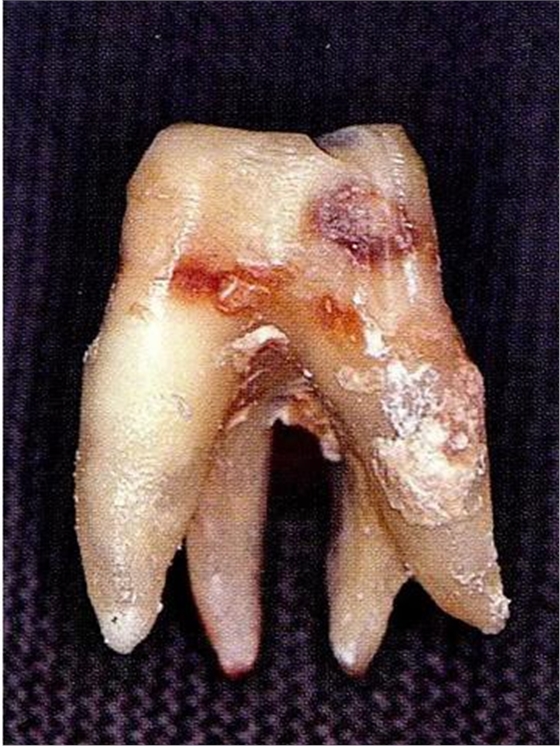

[融合牙]

▼圖6-4下頜第二后磨牙的融合根。在根尖的組合部的產(chǎn)生了附著喪失,導(dǎo)致急速惡化。